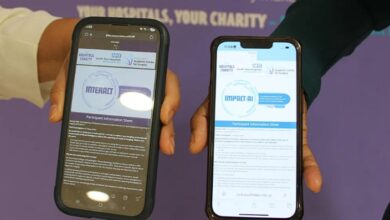

استبيان حول استخدام الذكاء الاصطناعي في تحليل الأشعة السينية: رأي المرضى مهم

يتم استبيان المرضى حول مدى رغبتهم في معرفة كيفية استخدام الذكاء الاصطناعي (AI) للمساعدة في تحليل أشعة المستشفيات. الدكتورة مايا…